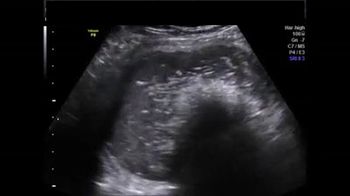

Challenge your diagnostic skills: See anything out of the ordinary in the kidneys of this third trimester fetus?